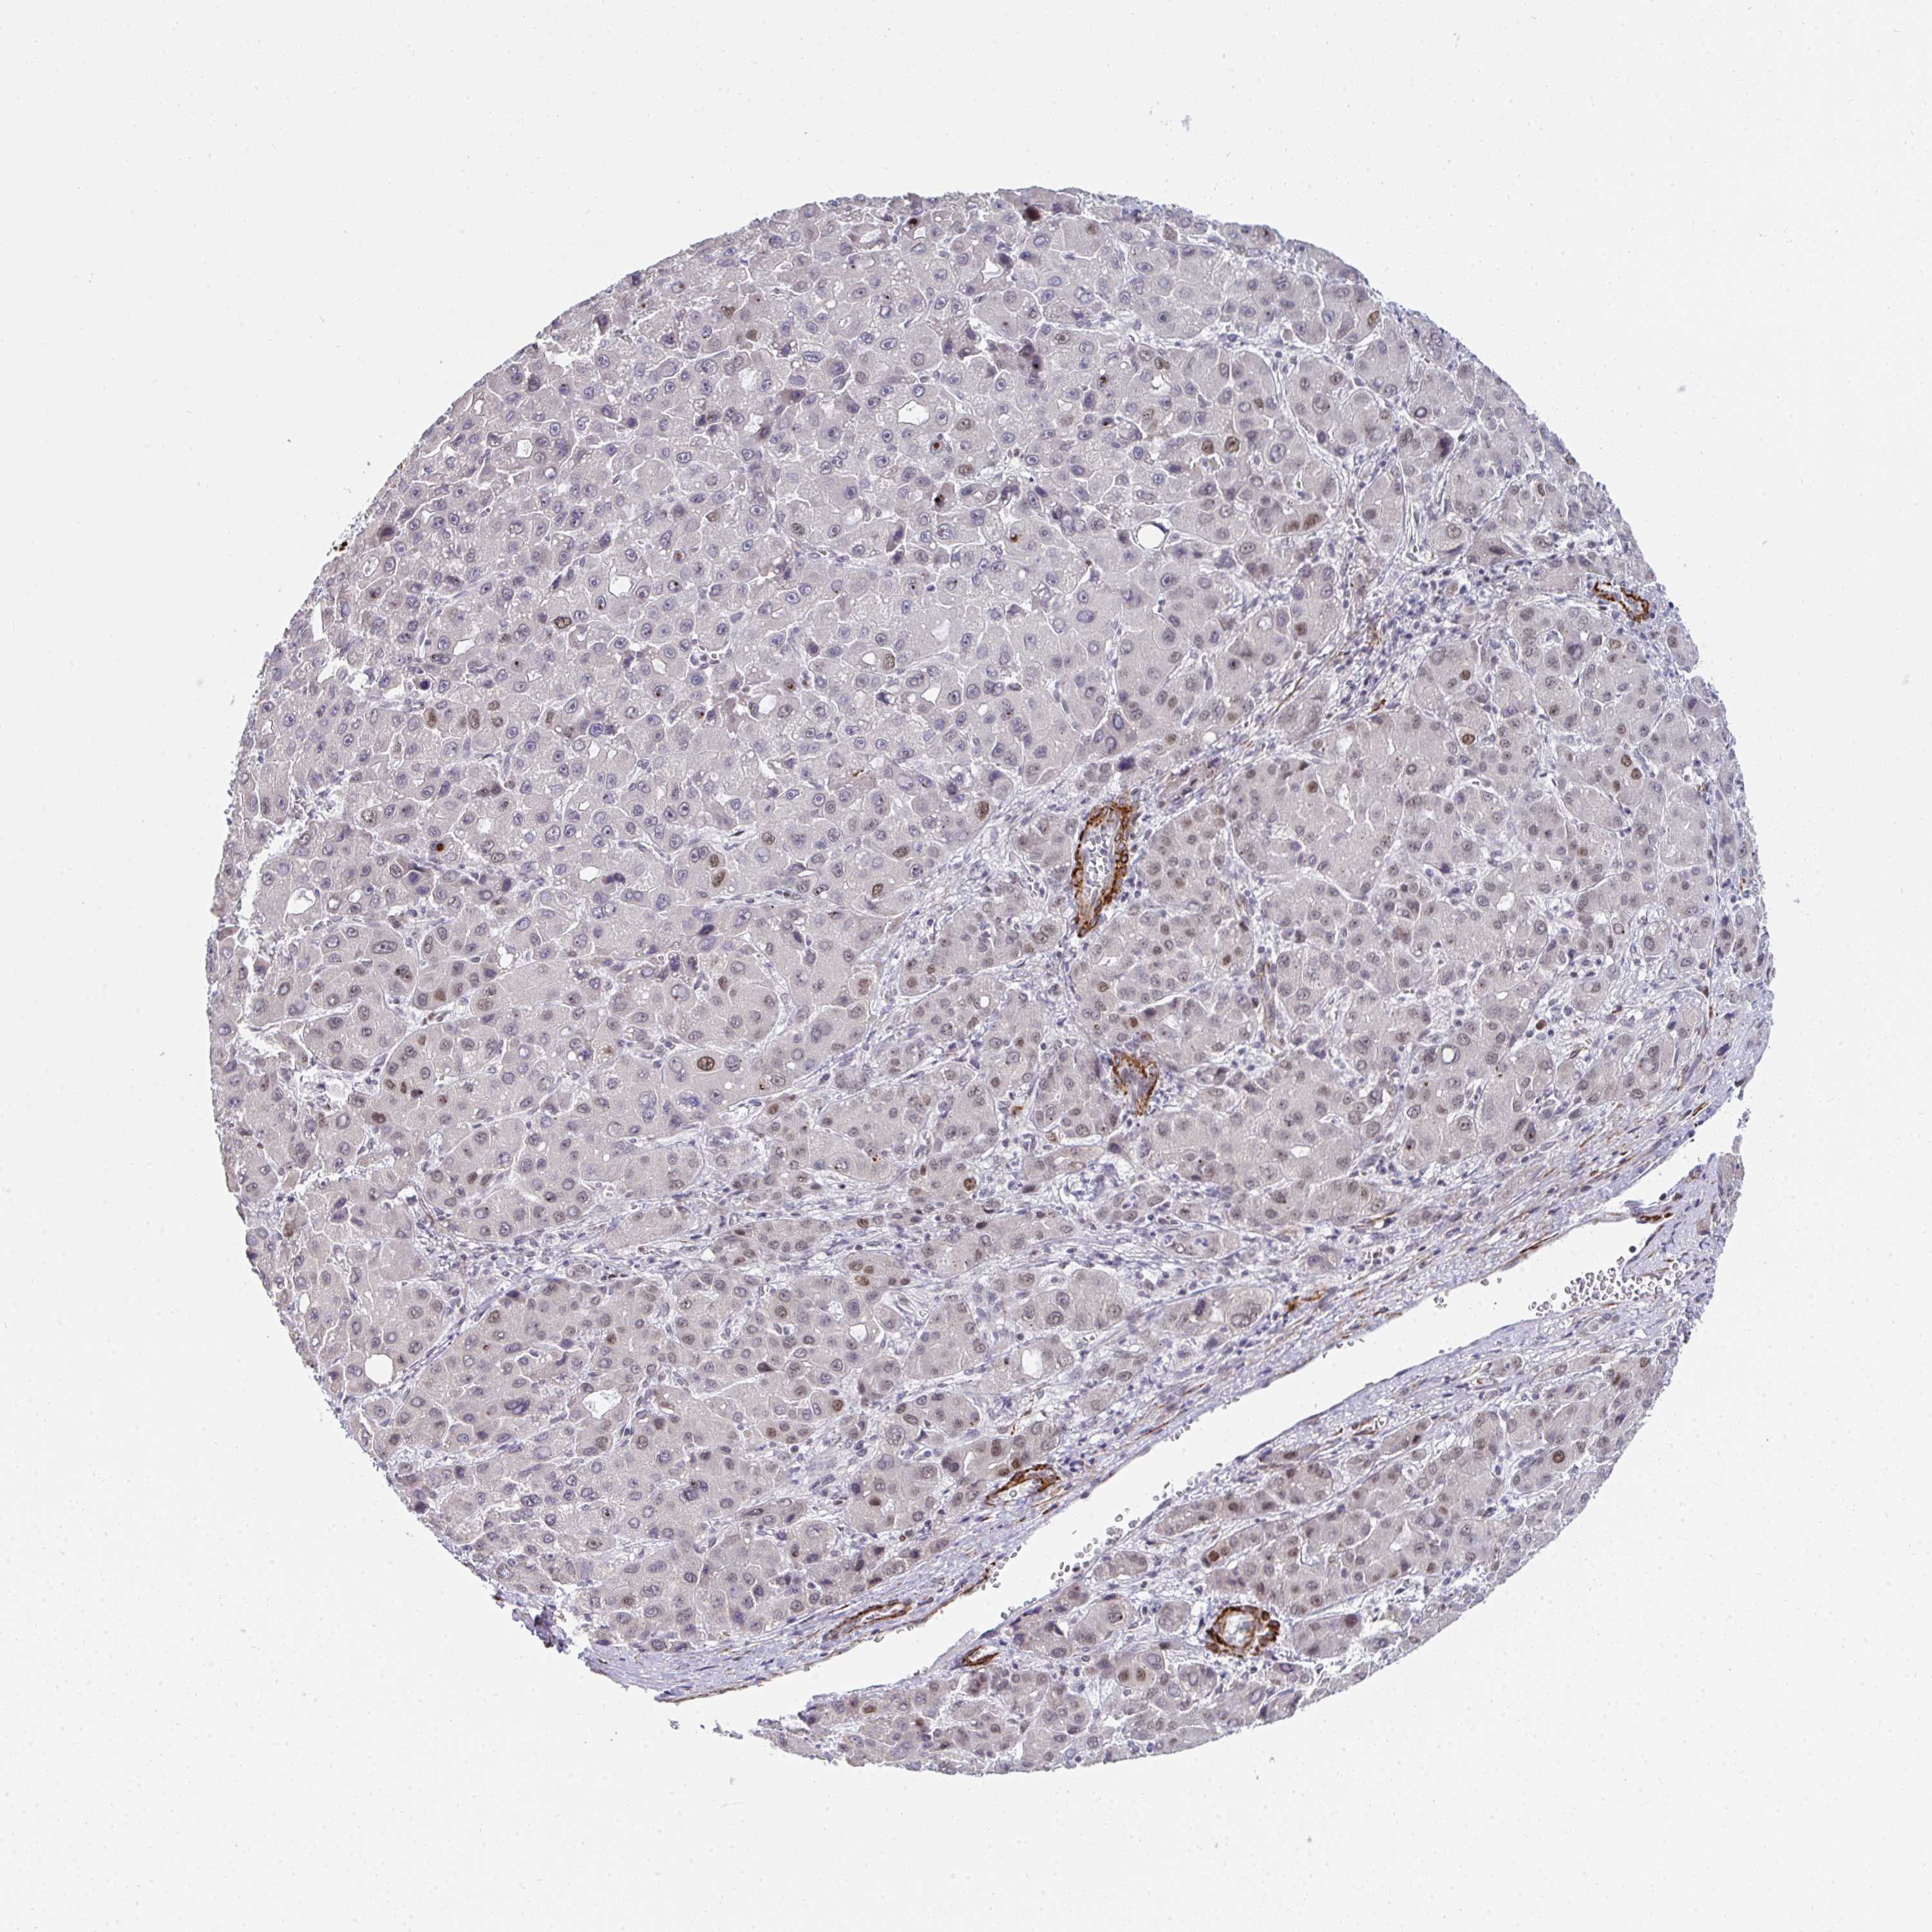

LIVER CANCER - Protein expressioni

A mouse-over function shows sample information and annotation data. Click on an image to view it in a full screen mode. Samples can be filtered based on level of antibody staining by selecting one or several of the following categories: high, medium, low and not detected. The assay and annotation is described here.

Note that samples used for immunohistochemistry by the Human Protein Atlas do not correspond to samples in the TCGA dataset.

Antibody stainingi

Antibody staining in the annotated cell types in the current human tissue is reported as not detected, low, medium, or high, based on conventional immunohistochemistry profiling in selected tissues. This score is based on the combination of the staining intensity and fraction of stained cells.

Each image is clickable and will lead to virtual microscopy that enables deeper exploration of all samples and also displays staining intensity scores, fraction scores and subcellular localization as well as patient and tissue information for each sample.

Antibody HPA057285

Staining

High

Medium

Low

Not detected

Intensity

Strong

Moderate

Weak

Negative

Quantity

>75%

75%-25%

<25%

None

Location

Nuclear

Cytoplasmic/membranous

Cytoplasmic/membranous,nuclear

Cholangiocarcinoma

Carcinoma, Hepatocellular, NOS